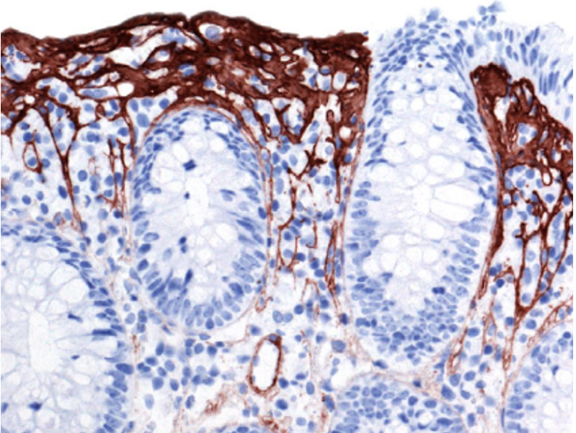

Vad visar kolonbiopsin?

- Förtjockat subepitelialt kollagenband och ökad halt inflammatoriska celler i lamina propria och bland enterocyterna. Förlust av bägarceller

- Mikroskopisk kolit/kollagen kolit

Vad ser du på den uppförstorade biopsin?

- Kollagen som omger kapillärer och innehåller inflammatoriska celler. Ytepitelet är degenerativt förändrat och uppvisar karaktäristisk avlossning

- Förlust av bägarceller

- Mikroskopisk kolit/kollagen kolit

Vad ser du på den uppförstorade biopsin?

- Visualisering av förtjockat kollagenband och att dess nedre del är oregelbundet

- Mikroskopisk kolit/kollagen kolit